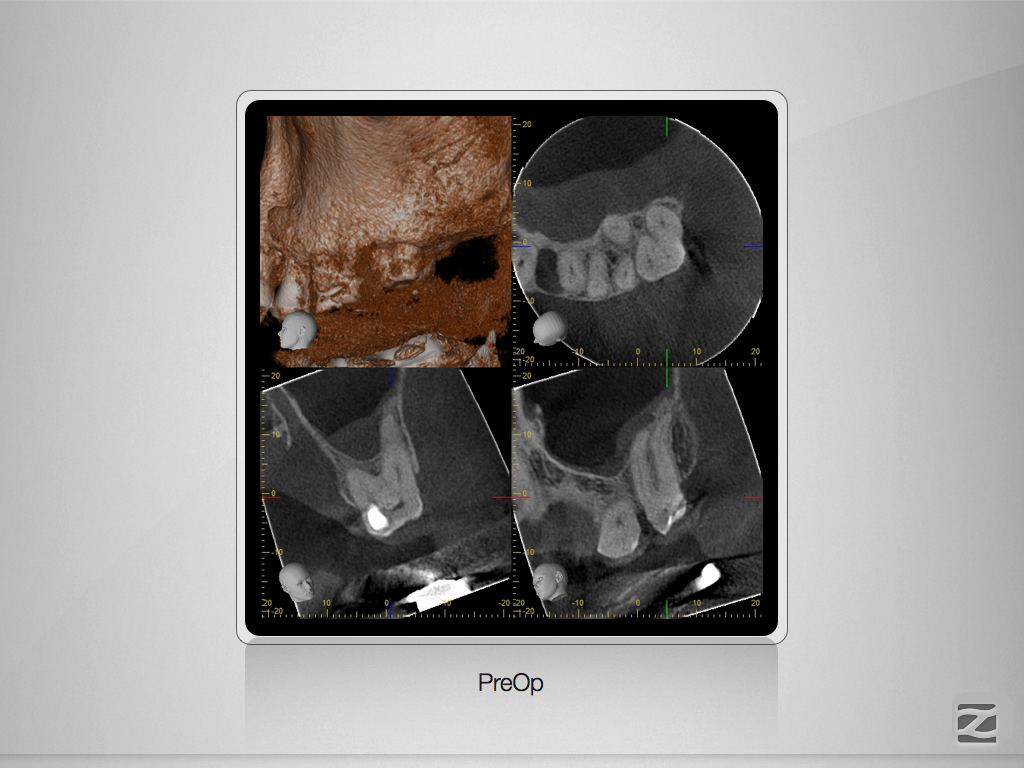

27D.002

Hyflex Fallbeispiel (3/3)